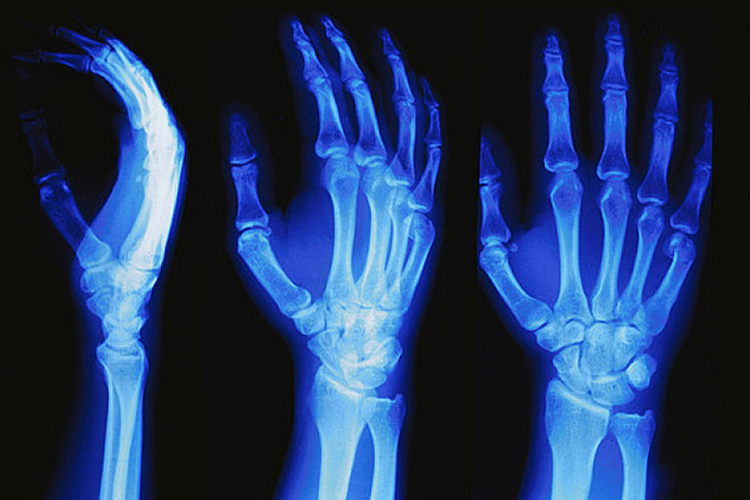

正常右手手腕X光片可以看到桡腕关节、腕骨间关节及桡尺远侧关节。清晰显示出其结构为15块骨(桡骨、尺骨、8块腕骨以及5个掌骨基底部)及它们构成的20个关节面。

手腕在手和臂之间,由8块腕骨构成,腕骨的活动空间并不大,但是腕骨之间能够进行某种程度的滑动和交错运动,所以手腕较为灵活。许多腕内关节也在腕骨周围,腕内关节通过小的滑动与旋转,促成手腕动作,对正常的手腕活动来讲非常重要。